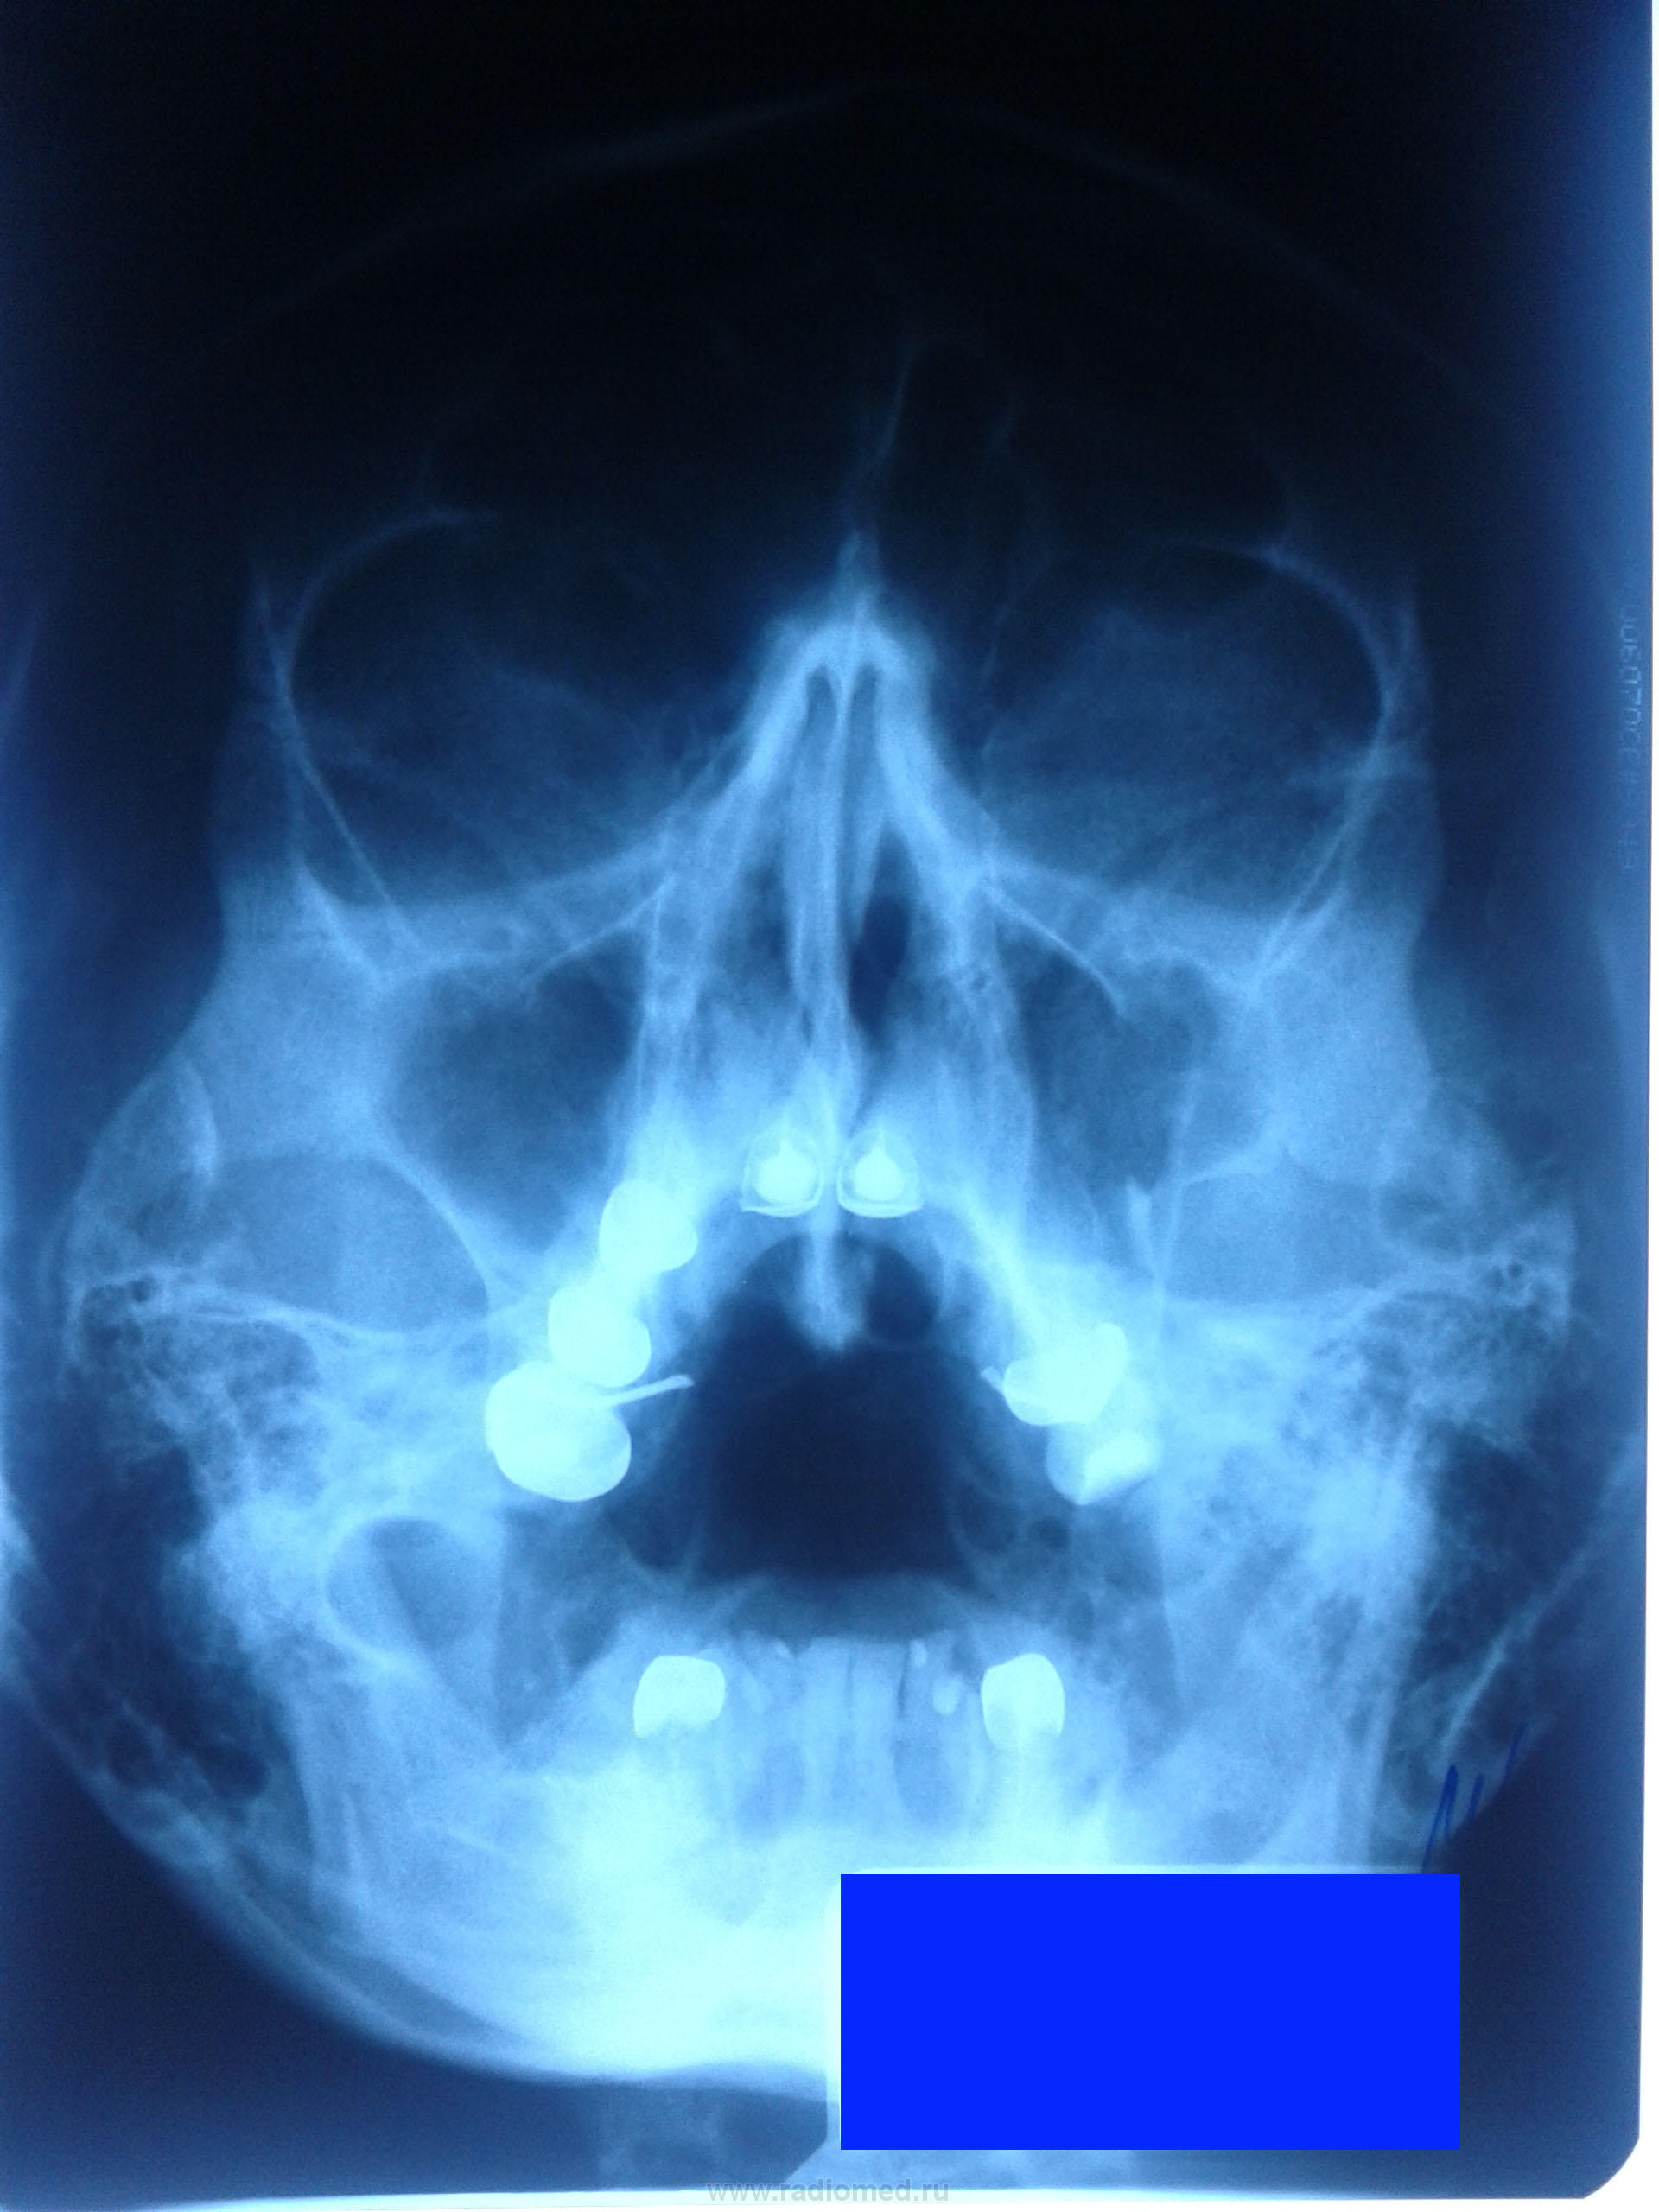

Подскажите начинающему: женщина, 1972 г.р., обследование по поводу возможного синусита. Меня смущает левая в/челюстная пазуха (стенки). Это вариант нормы? Или что-то приобретенное?

Очень похоже на посттравматическую деформацию (перелом со смещением) наружной стенки левой верхнечелюстной кости. Совсем недавно такой вот солдатик поступил (внеуставные, так сказать, разборки), сейчас прокурор им занимается.

Слева вдавление наружной стенки (травма?) в.челюстной пазухи. Справа- гайморит.

По поводу правостороннего гайморита вероятно имелось в виду некоторое утолщение слизистой оболочки латеральной стенки верхнечелюстной пазухи.

Перелом не только наружной стенки левой гайморовой пазухи, но, похоже, и нижней стенки левой орбиты.

Справа такая же  верхняя глазничная щель.

Согласен. Но там нет ступеньки. Для подтверждения делаю томографию.